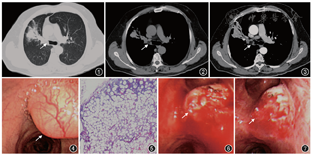

患者男,59岁,因“间断发热10余天”于2017年9月4日入院。该患者于入院10余天前无明显诱因出现间断性发热,体温最高达39.0 ℃,发热时伴大汗,口服退热药物后体温可恢复正常,4~6 h后体温再次升高,热前无寒战,无畏寒,周身无皮疹。病程中患者偶有咳嗽、咳痰,食欲、睡眠及精神状态尚可,二便正常,近期体重未见明显变化。既往史:高血压病病史2年,血压最高达180/110 mmHg(1 mmHg=0.133 kPa),平素规律口服苯磺酸左氨氯地平片(2.5 mg/次,1次/d)控制血压,血压控制尚可。吸烟30余年,20支/d。入院体检:右肺听诊呼吸音弱,右上肺未闻及明显呼吸音,心腹未见明显异常。辅助检查:胸部CT平扫+增强:双肺纹理清晰,右肺上叶支气管开口处可见结节状低密度影,增强扫描可见病灶轻度强化,纵隔未见肿大淋巴结,双侧胸腔未见明显积液(图1, 2, 3)。其余检查未见明显异常。

因患者胸部CT提示占位性病变,遂行纤维支气管镜以明确病变性质。第1次支气管镜检查见气管通畅,隆突锐利,右肺上叶支气管开口处可见新生物完全阻塞管腔,新生物呈结节状外生性生长,基底部较宽,质地柔软。肿物表面光滑,黏膜充血,可见表面毛细血管增粗、扭曲、扩张。周围黏膜略充血,水肿,软骨环模糊不清,并分布少量黏液性分泌物(图4)。于该部位行新生物活检术,钳检5块病变组织标本送病理检查。送检病理回报:右肺上叶开口支气管黏膜下脂肪组织增生,分化成熟,病变形态符合脂肪瘤(图5)。结合患者各项临床资料,诊断该病变为气管内脂肪瘤。遂行第2次气管镜进行内镜治疗,给予气管镜下电圈套器套取新生物后,利用氩等离子体凝固(APC)烧灼清理残存肿瘤组织,在破坏肿瘤细胞的同时加以止血(图6)。患者术后病情平稳,生命体征稳定,安全返回病房。术后3 d,再次气管镜检查,以清除坏死组织及焦痂,并再次烧灼残存肿瘤,镜下可见右肺上叶呈术后改变,新生物消失,右肺上叶支气管恢复通畅,残留少量损伤黏膜(图7)。入院时因胸部CT提示右肺上叶远端阻塞性肺炎,故住院期间同时给予抗感染治疗(哌拉西林钠舒巴坦钠,5.0 g,2次/d)。患者经内镜介入联合抗感染治疗,5 d后体温恢复正常,病情好转出院。